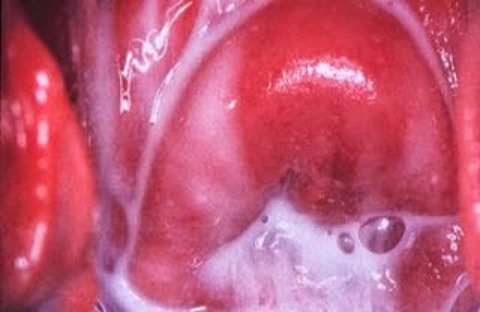

Ndiyo. Katika hatua za awali za ujauzito (wiki 1 hadi 12), mwili wa mwanamke huanza kubadilika haraka kwa sababu ya ongezeko la homoni kama estrogen na progesterone. Moja ya mabadiliko hayo ni kutokwa na majimaji meupe au ya uwazi ukeni, yanayojulikana kitaalamu kama leukorrhea.

Majimaji haya husaidia kulinda kizazi dhidi ya bakteria, kuuweka uke katika mazingira salama kwa ajili ya ujauzito kuendelea vizuri.